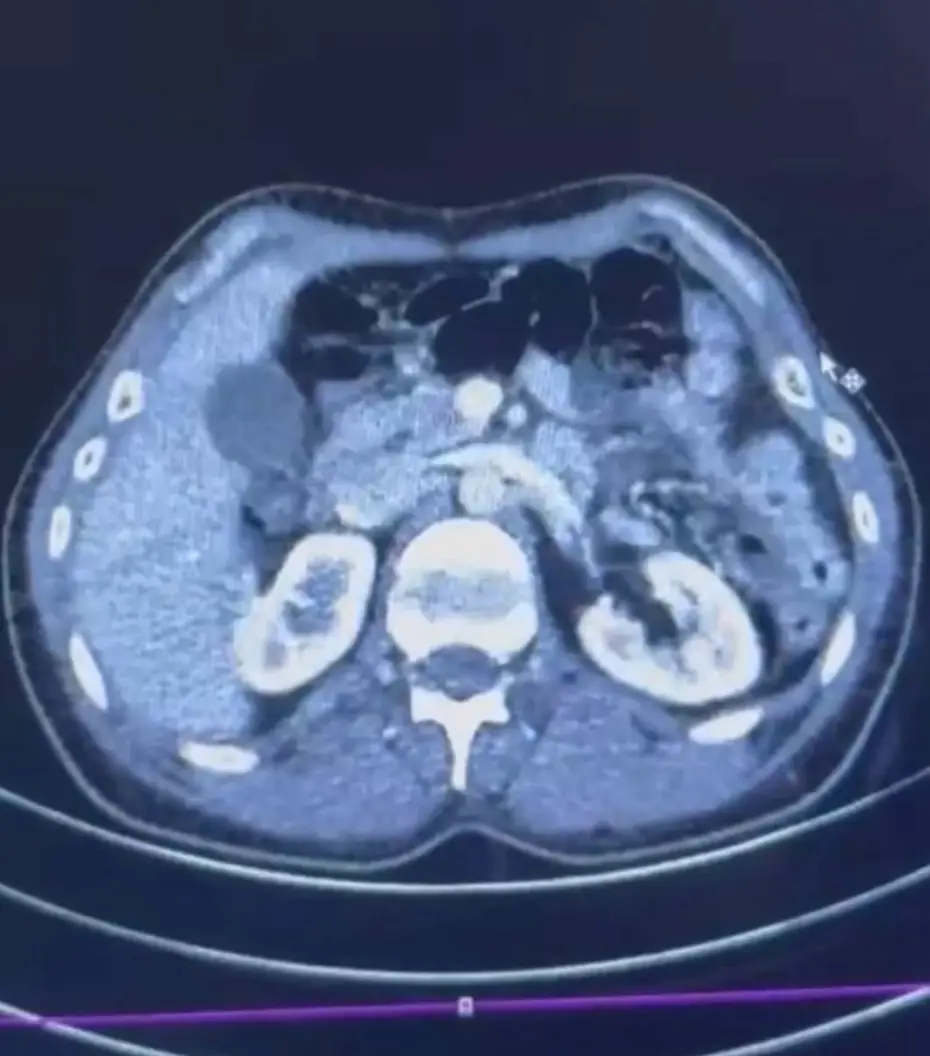

RÖNTGEN ÇEKİLDİ, KAPSÜLLER ORTAYA ÇIKTI

Şüphelilerden S.C. ve R.B.C. muayene edilmek üzere Kayseri Şehir Hastanesi'ne getirildi.

Röntgeni ve ultrason çekilen şüphelilerin midesinde yaklaşık 50 kapsülde 554 gram uyuşturucu olduğu tespit edildi.

Uyuşturucular sağlık ekiplerinin tedavisiyle çıkarıldı.